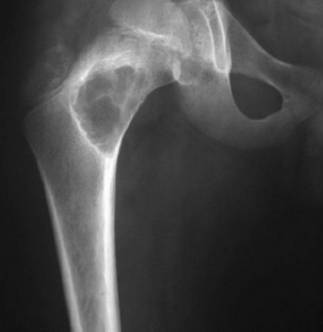

Остеома бедренной кости

Бедренная кость (особенно шейка бедра) ‒ наиболее распространенное место локализации остеоидной остеомы. Она состоит из расширенных сосудов, остеобластов и ткани самой кости. Может иметь центральную область минерализации или сосудисто-волокнистый край. Также, остеома способна сформироваться в любом месте в пределах кости.

На рентгенограмме выглядит как нормальная кость или выявляет утолщение.

Остеома бедренной кости – фото:

Следует знать, как выглядит остеома (фото, особенно на рентгене), поскольку внешне ее сложно отличить от более агрессивного онкологического образования.